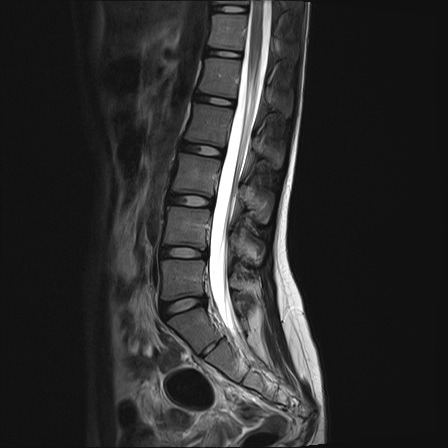

Compare the above image to this MRI of a healthy 20 year old lower back. It has lovely alignment, healthy vertebrae and discs, and a nice spacious spinal canal. You can see, based on my scan alone, how it would have been easy to give up hope and let the pain and fear set in. And let it control my life.